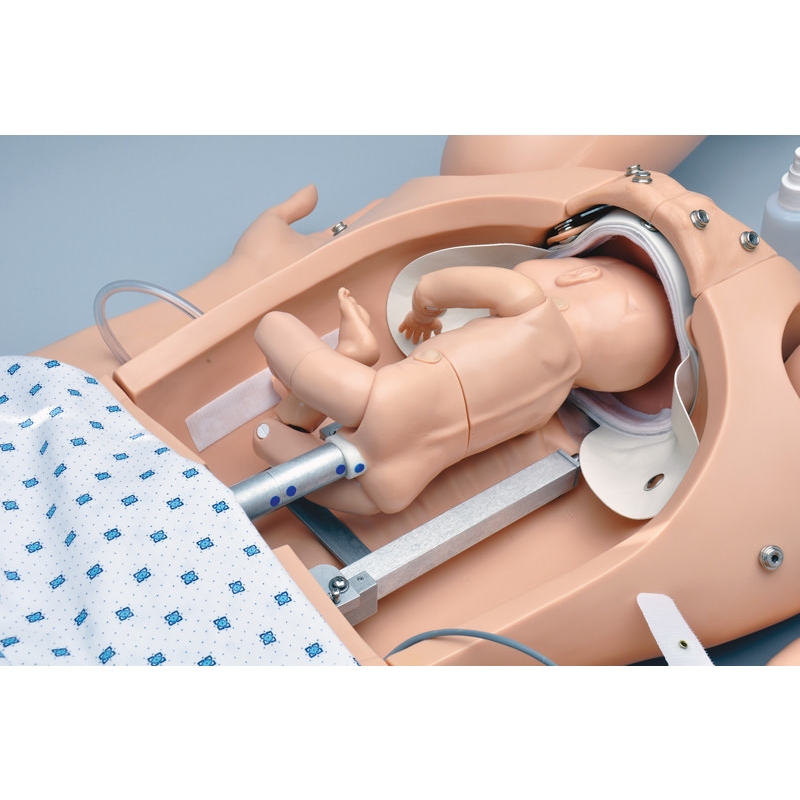

Noelle Simulator poroda mater in novorojenčkov

Zasnovan tako, da zagotavlja popolno porodno izkušnjo pred, med in po porodu.

- avtomatski porodni sistem

- merjenje spuščanja glave in razširitve materničnega vratu

- en premikajoč se porodni otrok s posteljico